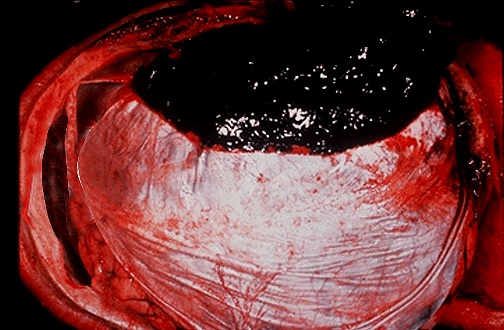

A blood clot is seen over the external surface of the dura. Thus, this is an epidural hematoma. Such a location for hemorrhage is virtually always the result of trauma that causes a tear in the middle meningeal artery. [Image contributed by Jeannette J. Townsend, MD, University of Utah] |